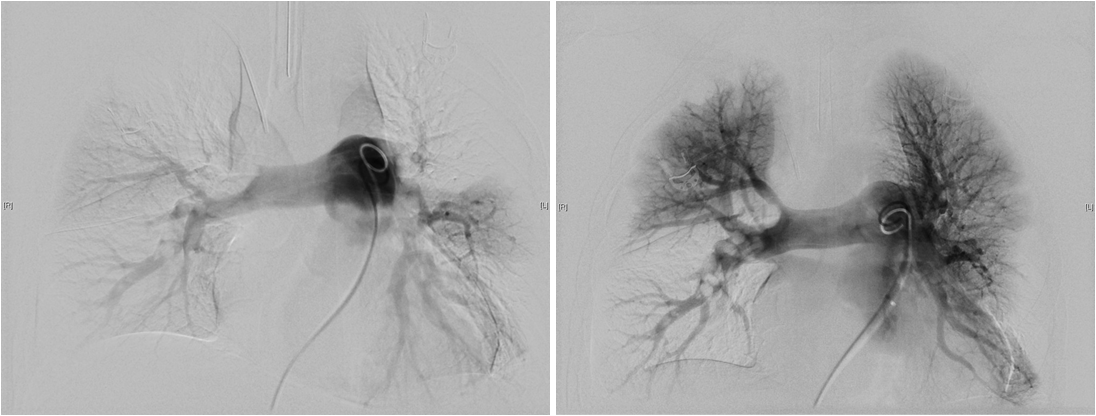

患者在急诊科治疗期间突发心跳呼吸停止,急诊医生给予心肺复苏后,气管插管呼吸机辅助通气,并运用了全身溶栓治疗,但全身状况一直不能好转,急请血管外科、重症监护室、麻醉科等多学科联合会诊,决定对患者进行肺动脉造影+置管溶栓术(Catheter Directed Thrombolysis; CDT)治疗,术前对患者进行了肺动脉CT检查评估,发现该患者双肺动脉主干均有大块栓塞,肺部仅剩五分之一血流畅通,右心扩大,心功能严重受损。情况紧急刻不容缓,经过与患者家属的高效沟通,医生将患者直接从CT室推入手术室,开始了争分多秒的手术。

患者肺部疏通前、后造影对比